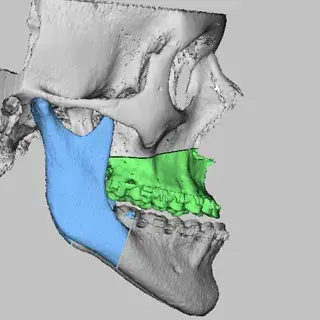

3D Systems' VSP® surgical planning solutions for craniomaxillofacial (CMF) applications received FDA clearance as a service-based approach to personalized surgery over 10 years ago.

3D Systems and Stryker Corporation have partnered to provide surgeons with best-in-class products and services for craniomaxillofacial surgeries. As a leader in personalized healthcare solutions, 3D Systems has planned and delivered devices for more than 140,000 patient-specific cases. The Stryker Craniomaxillofacial business specializes in providing patient-specific options and innovative solutions that help drive efficiencies in surgical suites. The combination of Stryker’s specialized team and advanced implants with 3D Systems' cutting-edge 3D printing technologies and expert consulting services positions both companies to provide a superior level of service to healthcare professionals who use these revolutionary solutions.